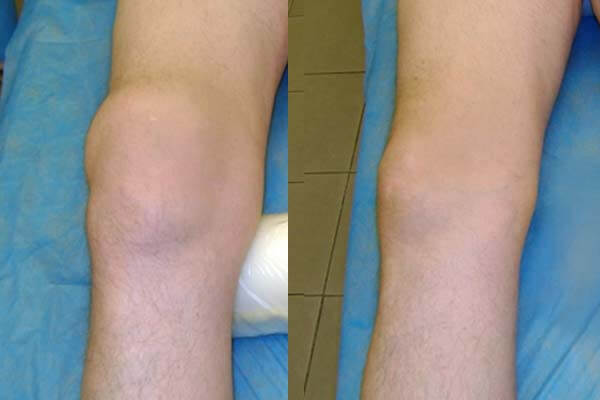

ผลลัพธ์การรักษาข้อเข่า

ผลลัพธ์การรักษาโรคข้ออักเสบที่มือ